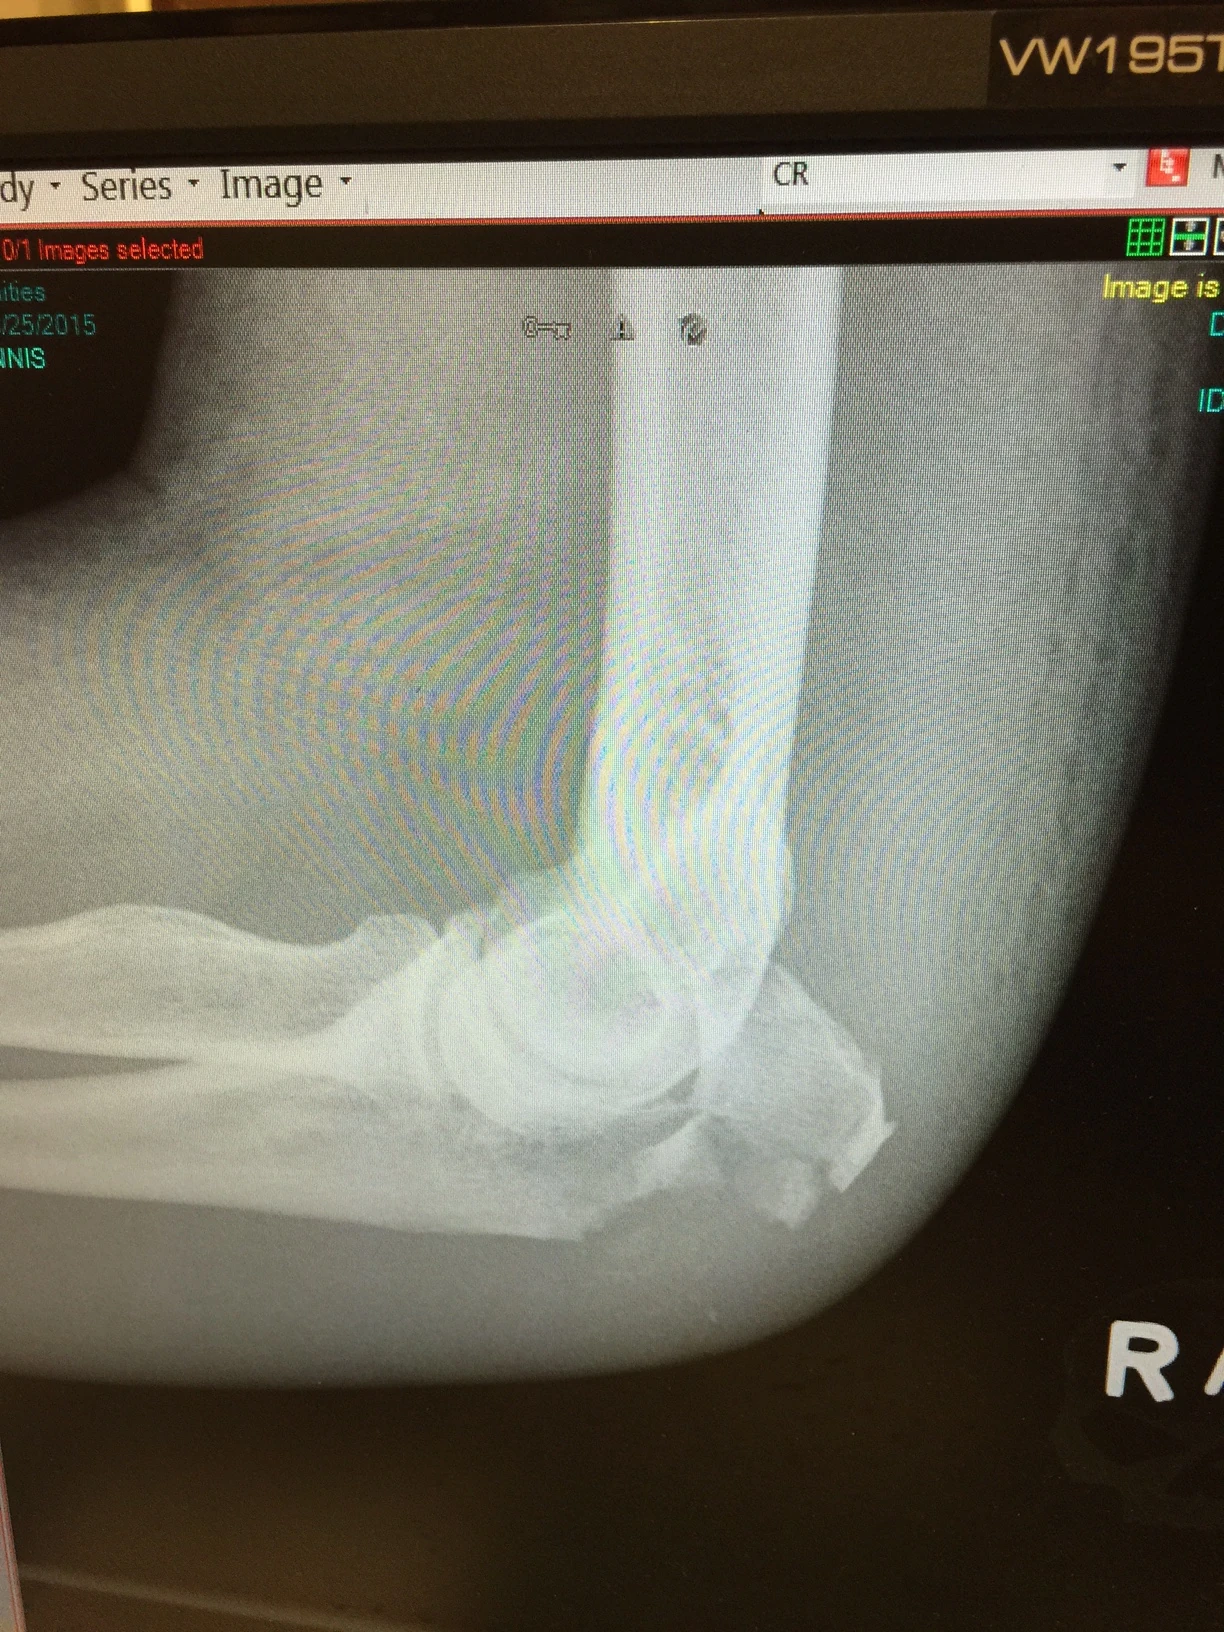

He didn’t have any pain and had been icing it a ton, but it kept swelling like crazy. So yesterday, he went by minor-med and got an x-ray. It is shattered, like broken into little tiny bits.

So, he needs surgery to repair it, which is going to happen tomorrow, in Lawrence. I was pretty surprised how smashed it was, considering, still now, he says it doesn’t hurt at all and he pretty much has full movement.

My elbow x-ray looked almost identical after getting doored going about 10 MPH on my singlespeeed MTB commuter bike. And it didn’t hurt either. Lots of swelling, but no real pain. Surgery was easy, too. Good luck to Dennis, I’m sure recovery will be swift and easy.